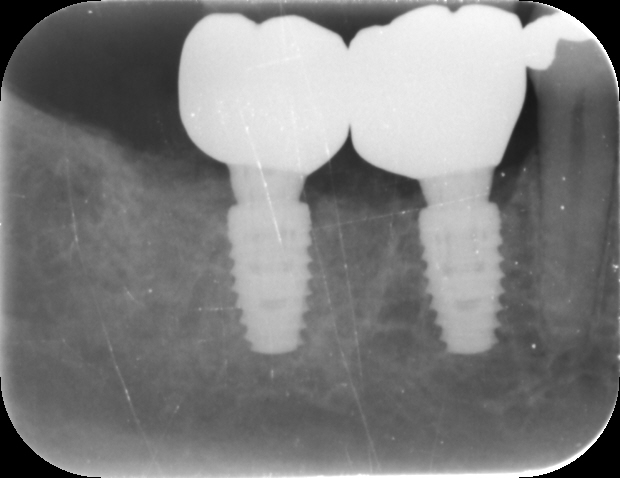

Fig. 2: Pre-op radiograph.

A 57-year-old male patient presented by referral with two failing molars, teeth #46 and 47. The patient had a clear medical history, and both molars exhibited extensive caries and restoration (Figs. 1–6).

Fig. 12: Post-op radiograph.

After a healing period of three months, the Medit i700 intra-oral scanner was used to record the implant position and soft-tissue profile, ensuring optimal prosthetic planning and precise restoration (Fig. 12). The implant crowns were constructed using custom milled titanium abutments with a zirconia crown. Care was taken to ensure that any zirconia in contact with the tissue was polished rather than glazed to promote optimal soft-tissue health.